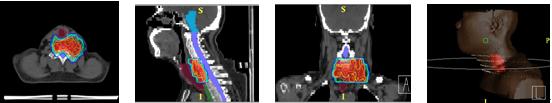

图示:该患者椎前恶性肿瘤,无法手术,由于周围重要正常组织较多,也无法应用常规放疗及X-刀和伽玛刀,治疗不当可能会产生截瘫等严重的并发症。患者只能应用调强适形放疗,调强放疗能很好的保护了脊髓及气管,等剂量图显示出及其优越的剂量分布(图示红色区域为肿瘤,紫色区域为脊髓,暗红色区域为气管)。经过治疗,该患者肿瘤得到很好控制。治疗中没有出现放射性肺炎和瘫痪症状。